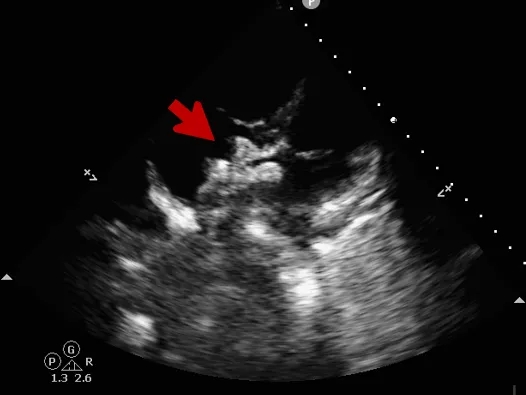

封堵器释放

撤出钢缆释放封堵器

超声下可见封堵器形态良好,封堵成功

释放后评估

封堵器位置正确、形态良好

彩色多普勒血流成像显示无残余分流存在

封堵成功